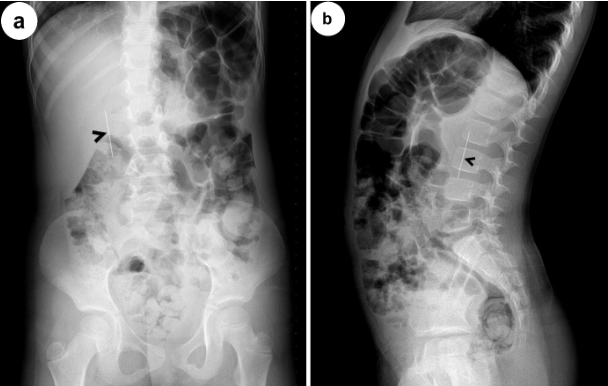

3yo girl ingested water beads. Now has abdominal pain, emesis. X-ray shows beads in large intestine. First-line management? Answer and learn more 👉 bit.ly/48ivJTe #imageofthemonth #quickpoll

JPGNonline's tweet image. 3yo girl ingested water beads. Now has abdominal pain, emesis. X-ray shows beads in large intestine. First-line management?

4 yo who swallowed a needle three hours ago goes to the ED. PE is unremarkable. Xray obtained. Where is the ingested needle most likely based on the X-ray? Answer and learn more 👉 bit.ly/3htf9YP?utm_so… #imageofthemonth #quickpoll

JPGNonline's tweet image. 4 yo who swallowed a needle three hours ago goes to the ED.  PE is unremarkable.  Xray obtained.

Where is the ingested needle most likely based on the X-ray?